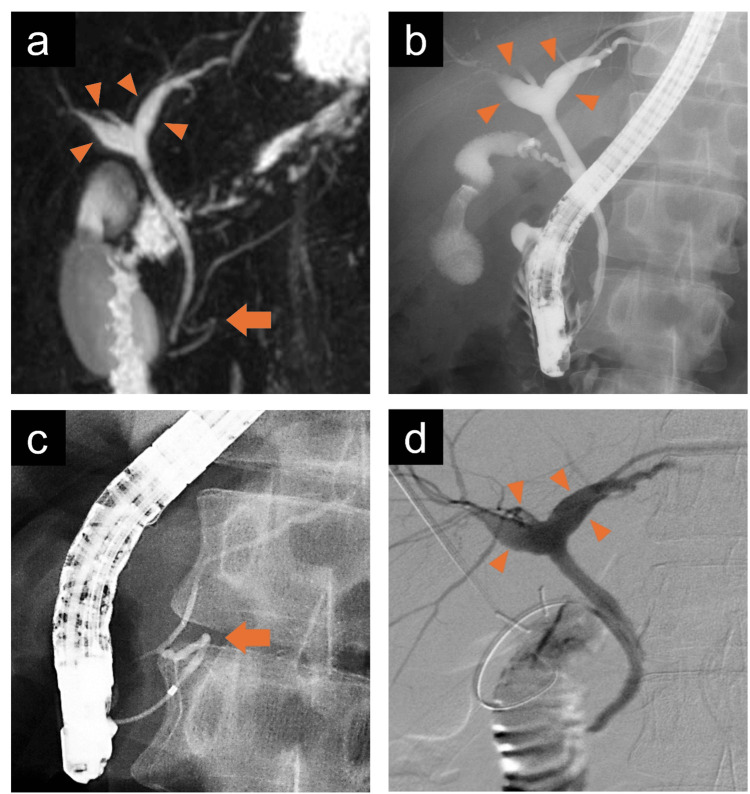

A 30-year-old man presented to our department with intermittent right upper abdominal pain occurring every few months for 10 years. He had a history of taking sodium valproate for epilepsy. He smoked approximately 20 cigarettes per day and had no history of alcohol consumption. Laboratory tests revealed neither inflammatory reactions nor elevated hepatobiliary enzyme levels. Contrast-enhanced computed tomography (CECT) showed a thickening of the gallbladder wall, suggesting chronic cholecystitis. Additionally, the right and left hepatic ducts in the hilar area were dilated, with a maximum diameter of 8 mm; however, the dilation of the extrahepatic bile duct was not significant (Figure 1). Similar to the CECT findings, magnetic resonance cholangiopancreatography (MRCP) showed dilation of the hilar bile duct. Furthermore, MRCP revealed flexed fusion between the ventral and dorsal pancreatic ducts (Figure 2a). Endoscopic retrograde cholangiopancreatography (ERCP) revealed the same findings, with mildly dilated hepatic ducts in the hilar area and an abnormally curved main pancreatic duct in the pancreatic head region (Figures 2b, 2c). During the ERCP, the collected bile showed an amylase level of 6,311 international units (IU)/L, exceeding the normal value of less than 1,000 IU/L [ref. 7]. Meanwhile, the lipase level measured 16,000 IU/L, for which the normal range remains undefined.

Based on these findings, diagnoses of CBD (an unclassifiable type according to the Todani classification), suspected PBM, and MMPD (inverted Z-shape) were made. Since the cause of the abdominal pain was presumed to be chronic cholecystitis due to the reflux of pancreatic juice into the gallbladder, we performed laparoscopic cholecystectomy and intraoperative cholangiography. The amylase and lipase levels in the gallbladder bile collected during the operation were 6,328 IU/L and 12,080 IU/L, respectively. Intraoperative cholangiography showed dilation of the hilar bile duct; however, there were no obvious findings indicative of PBM (Figure 2d). The macrofindings of the liver were normal. The operative time was 202 minutes. The postoperative course was uneventful, and the patient was discharged on postoperative day 4. Histopathological examination revealed chronic cholecystitis but no malignant disease. In the clinical follow-up at one year, there were no abdominal symptoms.